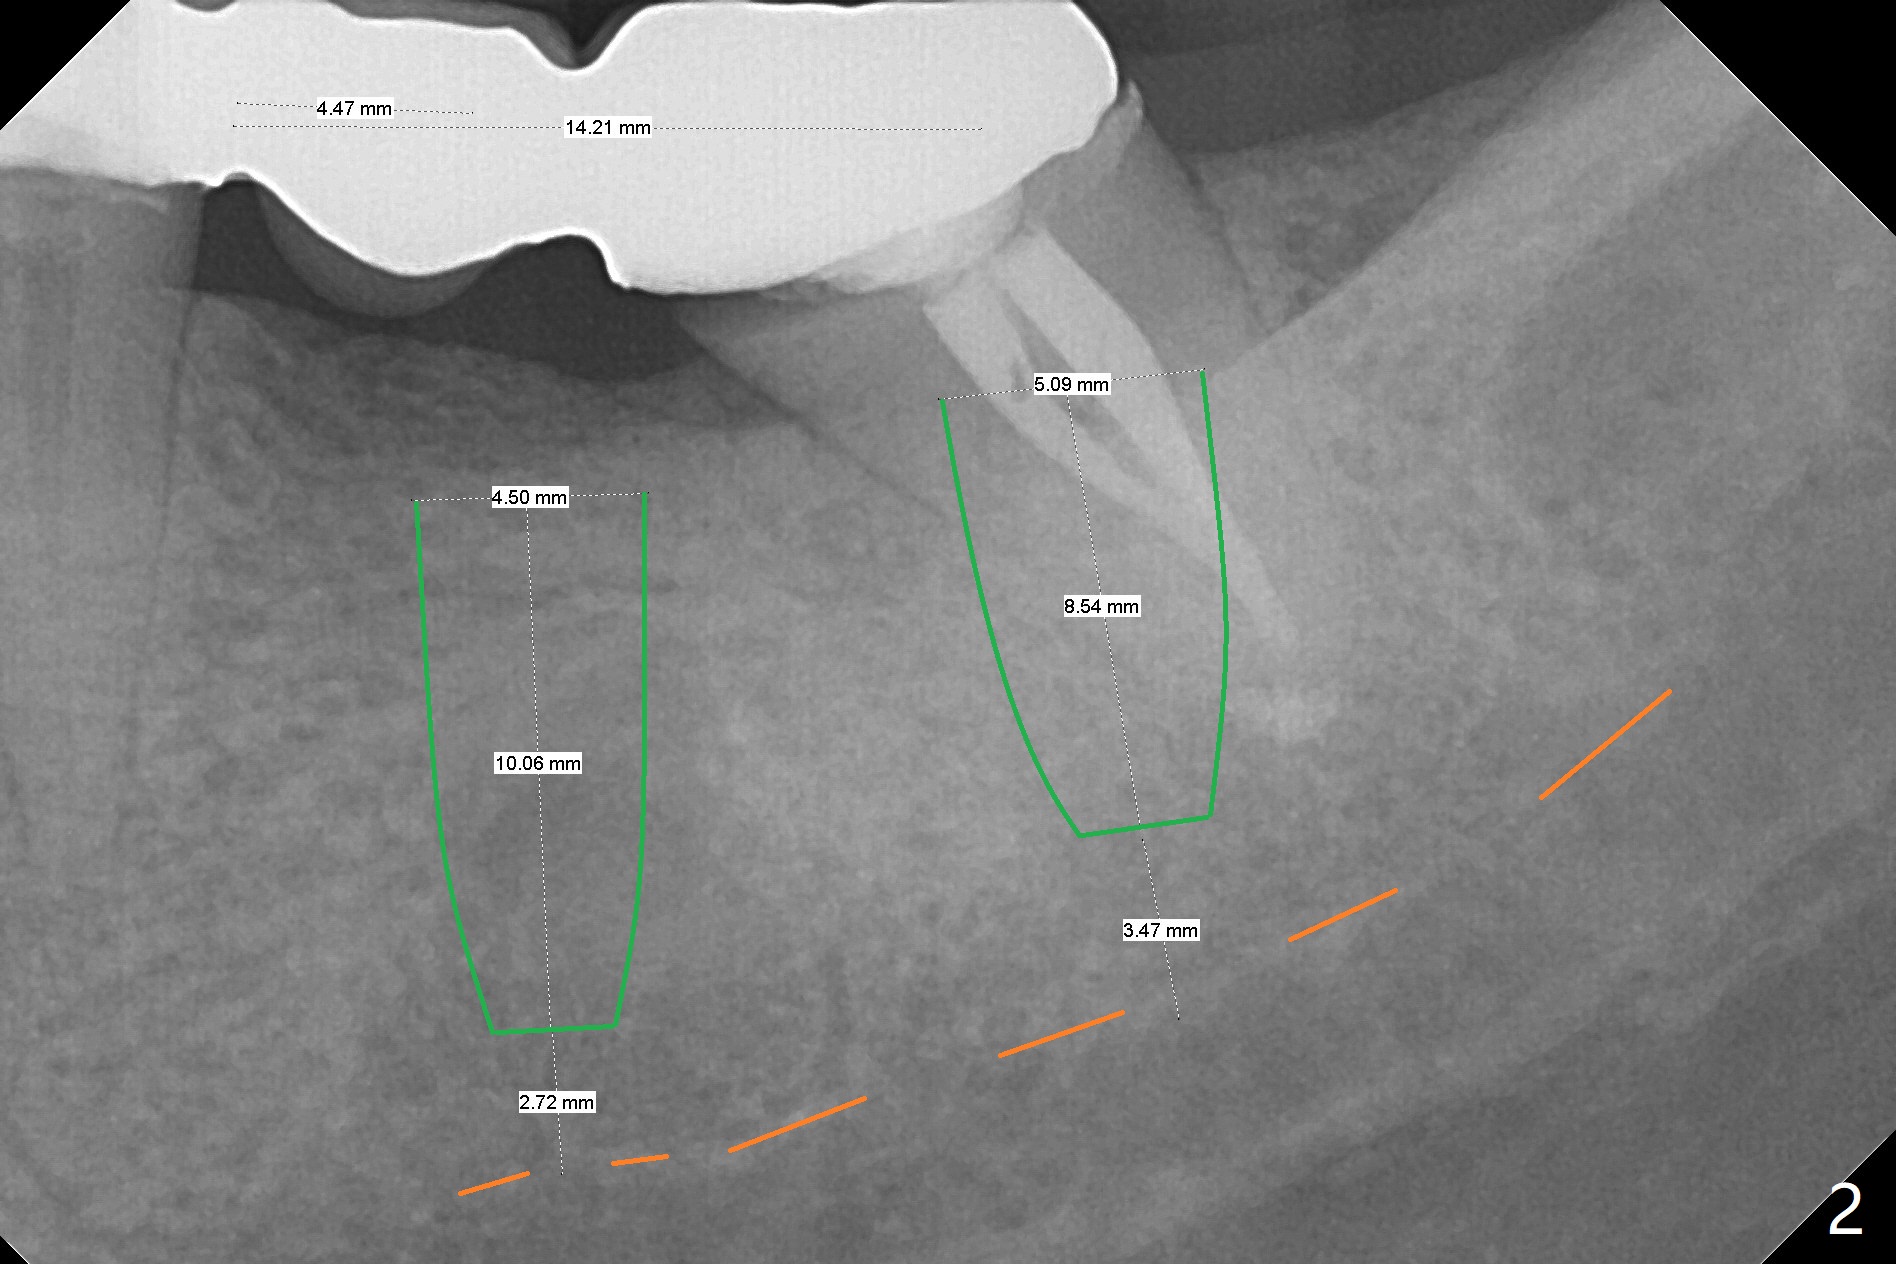

A 45-year-old woman returns to seek treatment for the recemented lower left FPD with open margin at #18 (Fig.1 *). It appears that two implants will be placed (Fig.2,3). Because of the narrow crest at #19, the ridge will be reduced before placement of a 4.5x7(4) mm Magicore (Fig.4). A 5x9(2 or 3) mm one will be placed in the mesial slope of the extraction socket (Fig.2,3,5). Alginate impression will be taken for wax up and surgical stent.